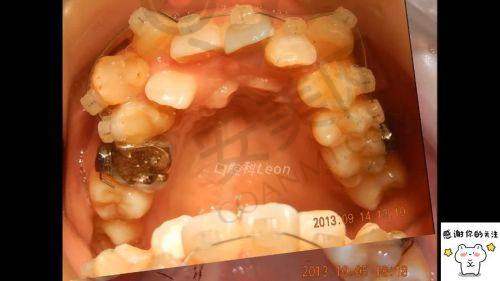

我第一次来到湛江柏乐口腔医院,刚走进大门,就有热情的导医接待了我。她询问了我的需求后,帮我挂了号,然后引导我到候诊区等待。在候诊的过程中,我观察了一下周围的环境,发现这里的卫生条件非常好,各个区域都打扫得一尘不染。轮到我就诊时,我见到了我的主治医生。医生非常和蔼可亲,他先是仔细地询问了我的牙齿情况和病史,然后对我的口腔进行了全方面的检查。之后,医生安排我去做了一系列的检查,包括X光片、牙齿模型等。这些检查都是为了更正确地了解我的牙齿状况,以便制定出更适合我的矫正方案。整个初次就诊的流程非常顺畅,工作人员的服务也特别周到,让我感觉特别安心。

在所有检查结果出来后,医生把我叫到了办公室,和我详细地沟通矫正方案。医生拿着我的X光片和牙齿模型,一边给我讲解我的牙齿问题,一边给我分析不同矫正方案的优缺点。他告诉我,我的牙齿不仅排列不整齐,还有一些咬合问题。针对我的情况,医生为我推荐了两种矫正方案,一种是传统的金属牙套矫正,另一种是隐形矫正。医生耐心地给我解释了这两种方案的特点。金属牙套矫正价格相对较低,矫正成效也比较稳定,但外观上不太美观;隐形矫正则更加美观、舒适,可自行摘戴,但价格相对较高。医生还根据我的个人需求和经济状况,帮我分析了哪种方案更适合我。更终,我结合自己的实际情况,选择了隐形矫正方案。整个方案制定的过程中,医生充分尊重了我的意见,让我感受到了他们的专精和负责。